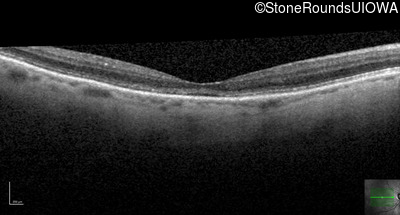

The clinical features favoring the diagnosis of RP1L1-associated occult macular dystrophy include: reduced acuity with a near-normal ophthalmoscopic appearance, a history of normal acuity in childhood; and, a "moth-eaten" appearance of the macular ellipsoid zone on OCT.

OD OS